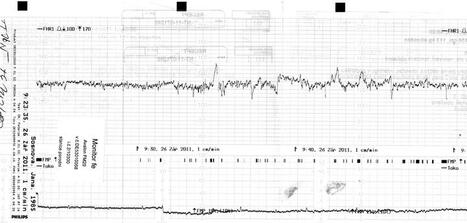

6.9.2011 sepsání porodopisu v porodnici + natočen monitor

15.9.2011 kontrola u dr. vše OK, monitor prý ukázkový, malá se hodně předvedla, až se všichni divili, jaká je zrovna akční. CS stále 5, hrdlo ještě uzavřené

22.9.2011 kontrola u dr. vše OK, monitor dobrý, malá se opět předvedla, CS 7, hrdlo otevřená na 2cm, propustné pro prst, předána od 26.9. do péče v porodnici

26.9.2011 kontrola v porodnici, natočen monitor, změřena i teplota, prohlídka doktorkou, vše OK, další KO 30.9.2011, pokud neporodím, stále otevřená na 2cm